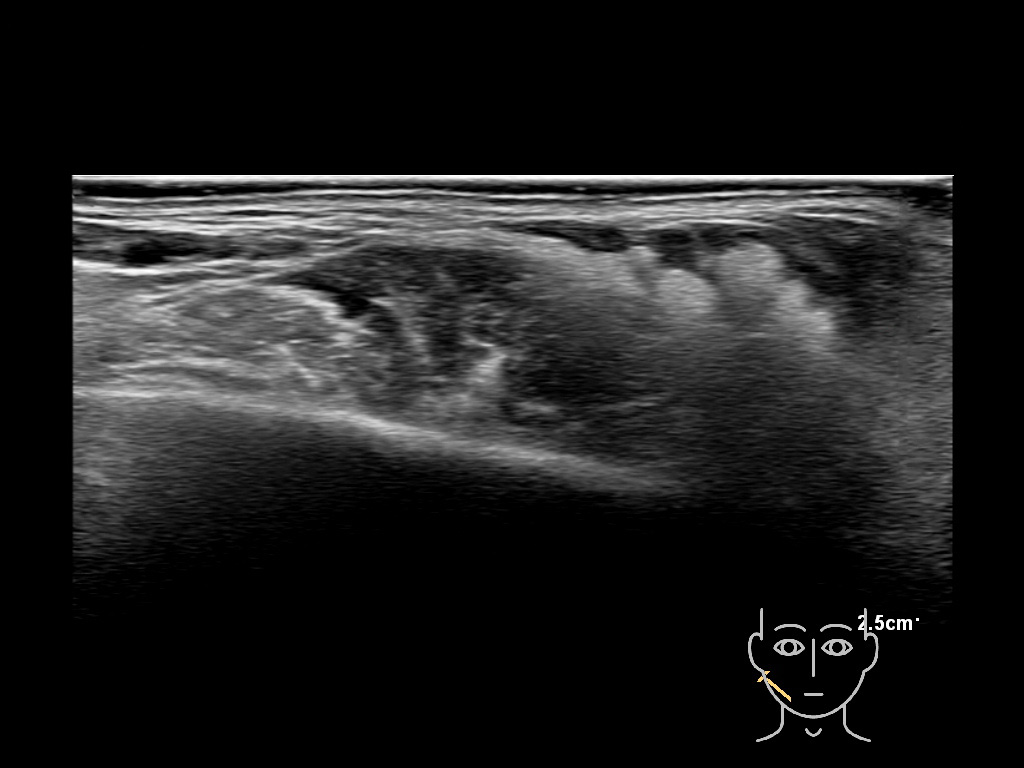

Draw in the second image below where the fillers are located. To check if your answer is correct, swipe the first image to the right.